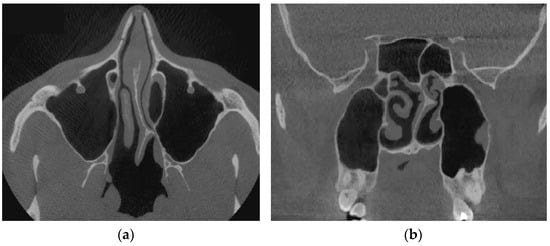

Verification of rhinomanometric data should be performed on the basis of tomographic data of the conditional norm and pathological conditions, which, due to various factors, affect nasal aerodynamics in different ways. Thus, in Figure 12 it is possible to see the characteristic tomographic sections of the nasal cavity at the conditional norm in the axial (Figure 12a) and frontal (Figure 12b) planes.

Figure 13 shows tomographic data of a patient with a curvature of the nasal septum to the left in the middle section, where you can clearly see a large change in configuration in the middle section of the nasal cavity on both axial (Figure 13a) and frontal (Figure 13b) sections.

Figure 14 provides a visualization of the local curvature of the nasal septum to the left in the posterior part of the nasal cavity, which is displayed on the axial—see Figure 14, and the frontal—Figure 14b tomographic sections.

Figure 15 shows the thickening of the nasal mucosa in chronic rhinosinusitis, which leads to narrowing of the airways (see Figure 15a,b).

Figure 16 demonstrates the state of the nasal cavity with adenoid vegetations, which can be seen in the images of characteristic sections in axial (Figure 16a) and sagittal (Figure 16b) projections.

Figure 17 represents tomographic data of a patient with empty nose syndrome after bilateral conchotomy. The removal of the lower shells and enlarged air space in the nasal cavity are clearly visualized in the axial (Figure 17a) and frontal (Figure 17b) projections.